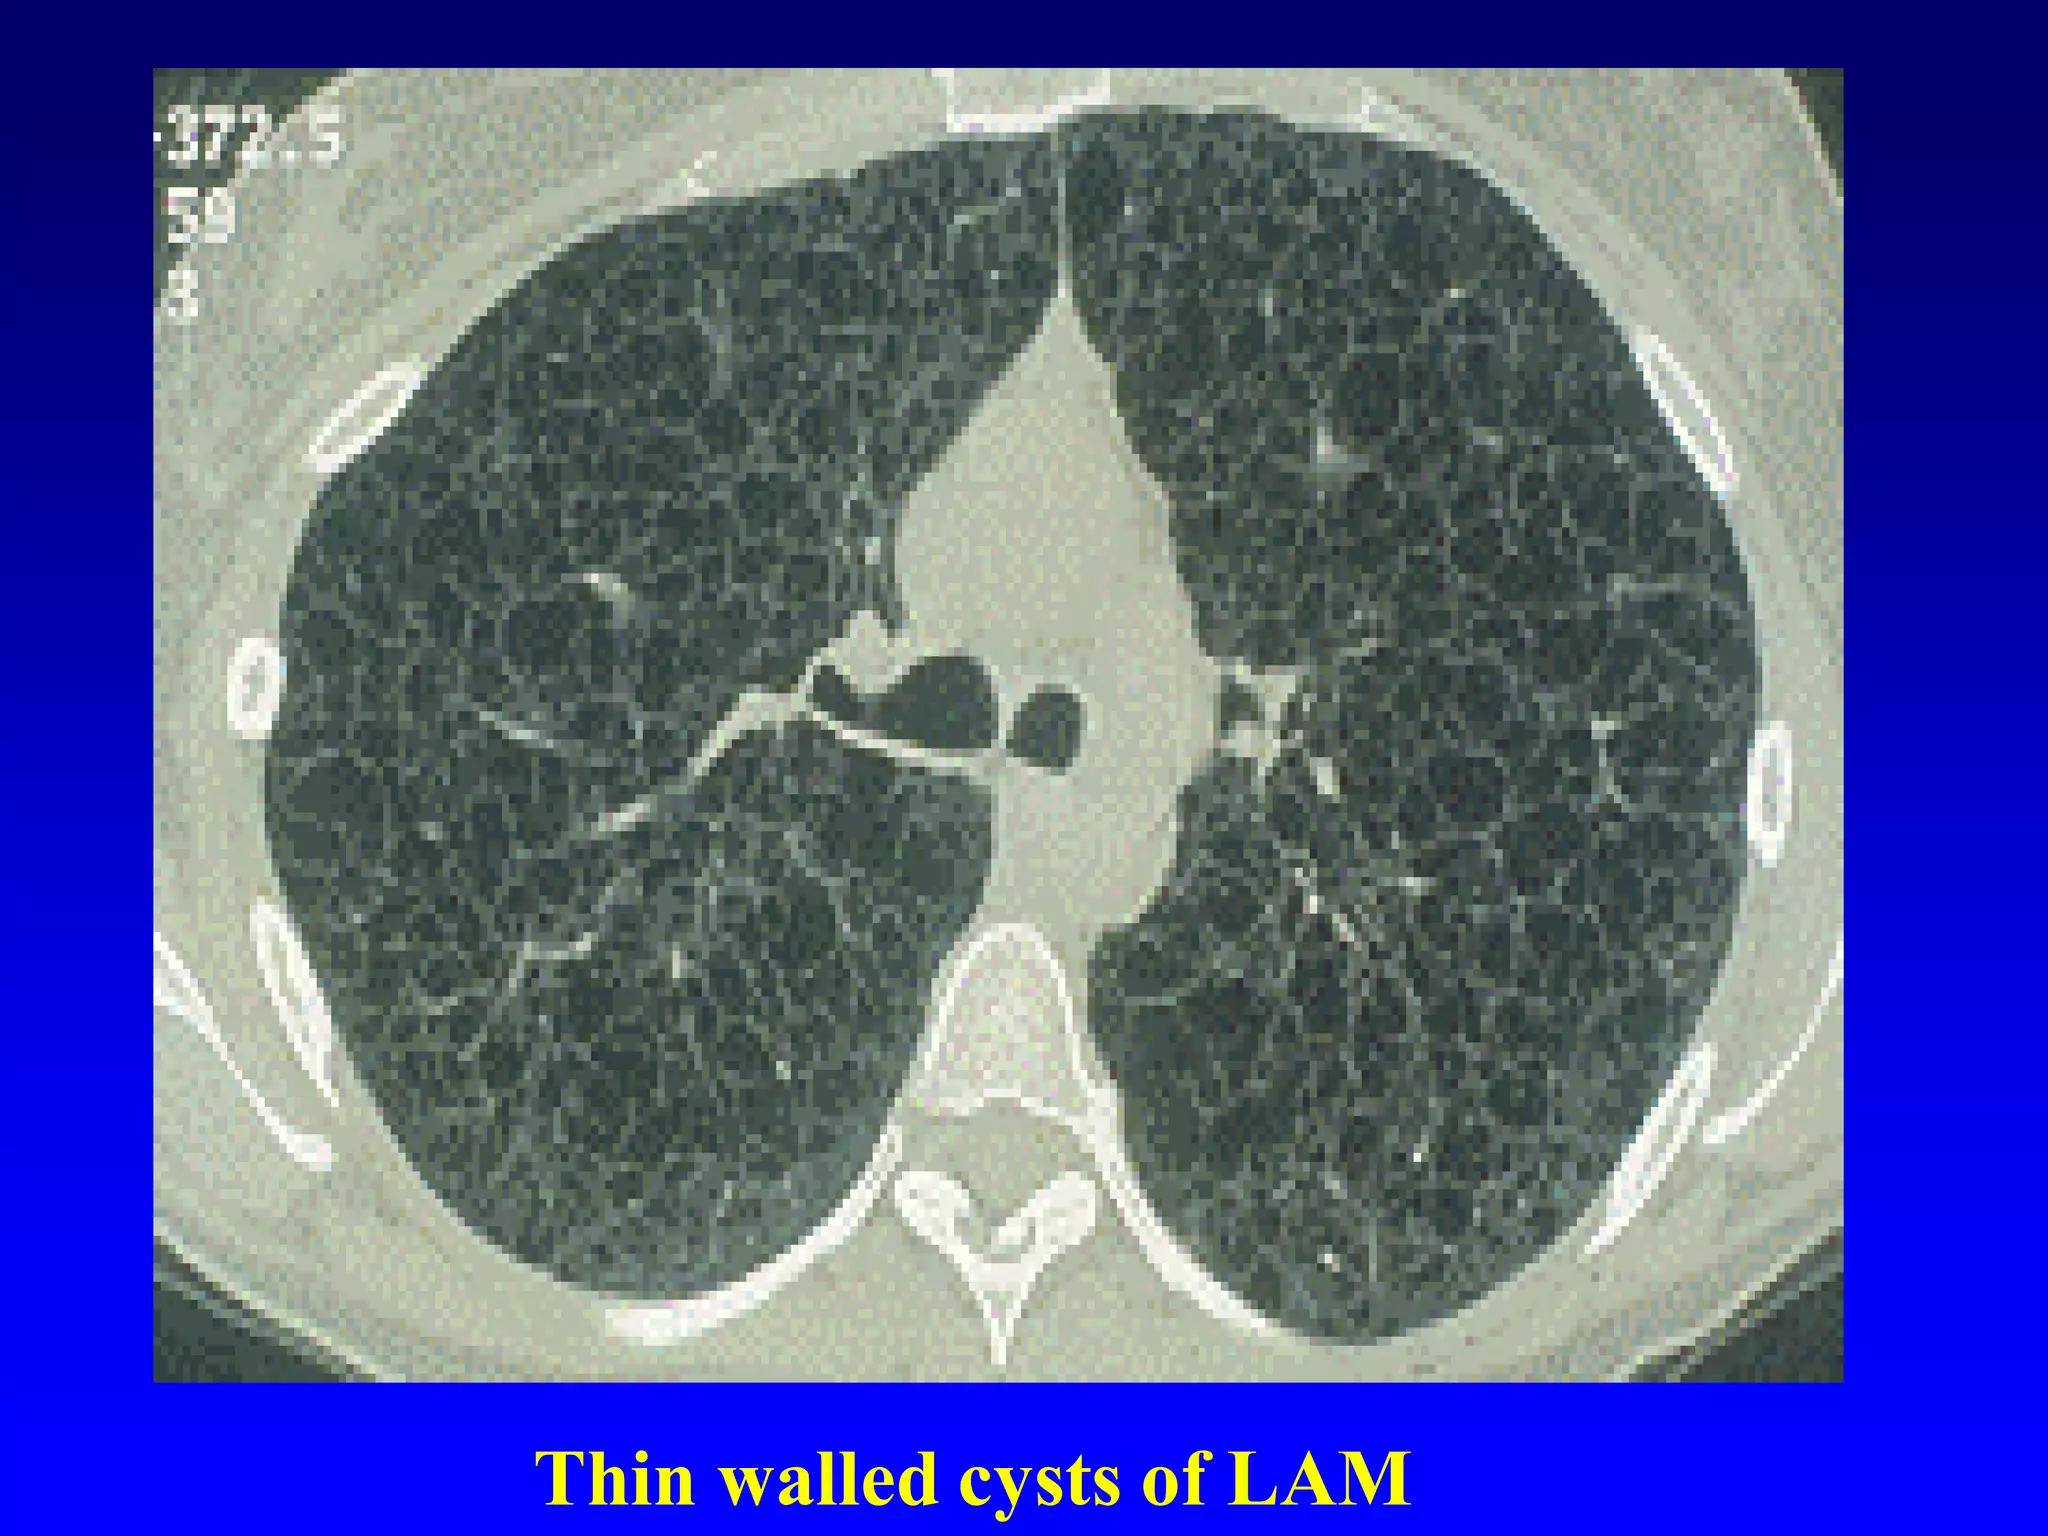

Thin walled cysts of LAM

Cyst

A cyst appears as a round parenchymal

lucency or low-attenuating area with a

well-defined interface with normal lung.

Cysts have variable wall thickness but

are usually thin-walled (2 mm) and

occur without associated pulmonary

emphysema . Cysts in the lung

usually contain air but occasionally contain

fluid or solid material. The term is

often used to describe enlarged thinwalled

airspaces

in

patients

with

lymphangioleiomyomatosis or Langerhans

cell

histiocytosis

;

thickerwalled

honeycomb cysts are seen in patients with

end-stage fibrosis .